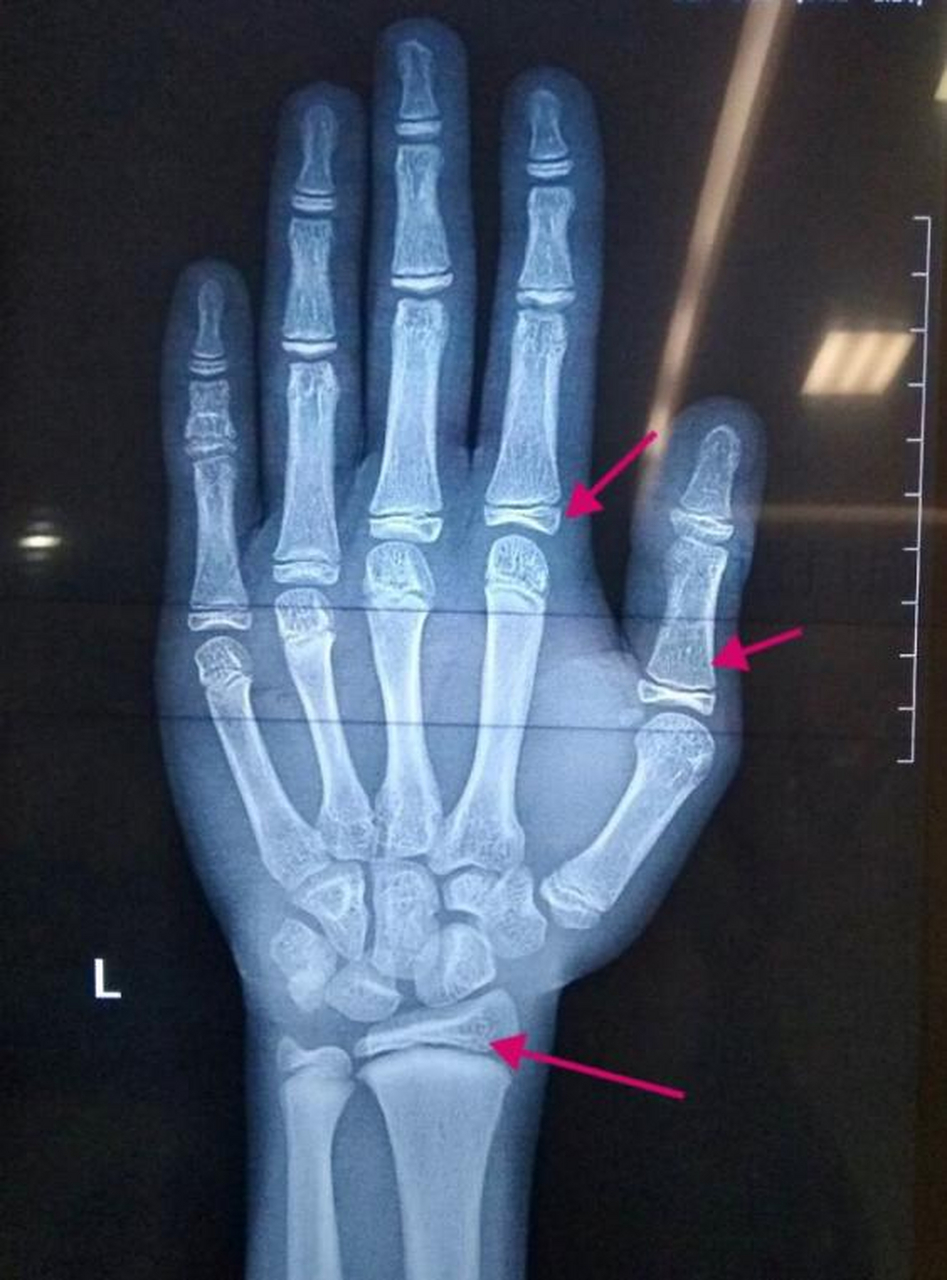

最近一位家长私信我,给我看他孩子拍摄的手部x光片,图片上显示骨骺线

他晒了两张手掌的x光片,确实伤得还蛮重,手背上一根骨头完全骨折,痕迹

我这有张x线片子,手部的,谁能帮着看一下

手掌x光图片看骨龄